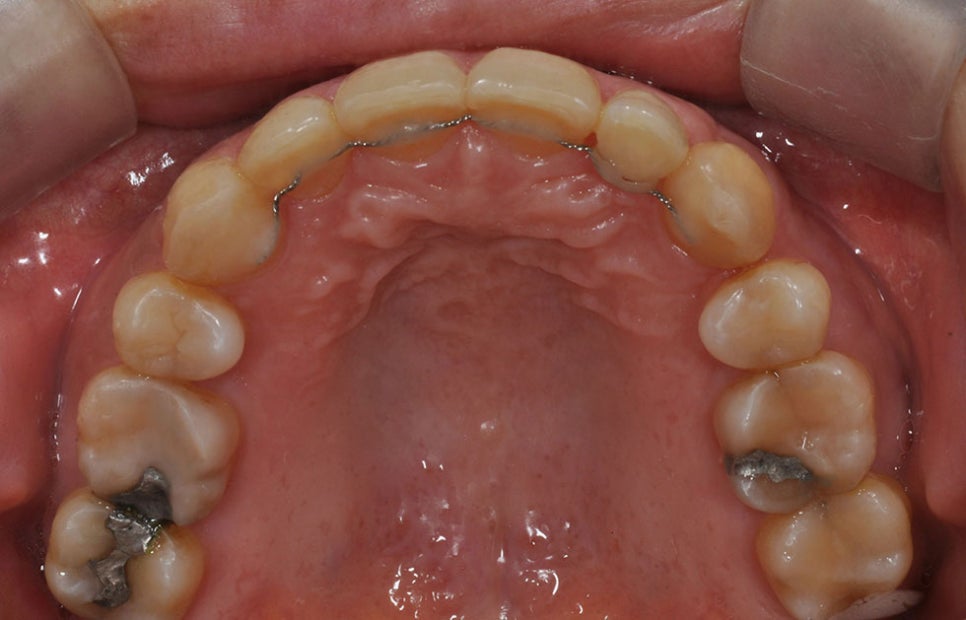

이에 대안으로 제시되는 교정 장치가

바로 투명 교정 장치(Clear Aligner)입니다.

투명 교정 장치는 치아 모양의 얇은

투명 플라스틱으로 마치 운동선수들이

착용하는 마우스피스처럼 생긴 장치입니다.

이를 치아에 끼우고 일정 기간마다

교체하면서 원하는 위치로 조금씩

이동시켜 교정을 시행합니다.

이때 서초동치아교정잘하는곳 저희 뉴엔의

투명 교정 장치는 치열을 3D 이미지로

스캔하고 심도있게 치아 이동 계획을

세운 뒤 치아 형태에 맞춰 제작합니다.

투명 교정 장치는 기존 철사 교정 장치의

단점을 상당 부분 해소하며 강한 힘이

아니라 알맞은 힘을 필요한 방향으로

가해주는 덕분에 통증이 덜합니다.

또한 투명하기 때문에 교정 장치 착용

여부를 쉽게 인지할 수 없어 어린 학생이나

직장인도 마음 놓고 착용할 수 있습니다.

치아 위생 관리도 용이합니다. 쉽게 빼고

끼울 수 있기 때문에 음식을 가릴 필요도

없고 양치질도 평소처럼 할 수 있습니다.

치아교정을 한다고 해서 충치나 잇몸

질병이 증가하지 않는다는 점에서 과연

획기적인 치료법이라 할 수 있습니다.

뉴엔의 형상기억 특허

보통 투명교정장치는 단계별로 1~2주씩

쓰면 형태가 변형되거나 교정력이

느슨해질 수 있는데, 뉴엔치과 투명교정

장치는 위의 영상에서 확인할 수 있듯이

뜨거운 물에 넣으면 물렁해졌다가

상온에서 서서히 처음 형태로 복원이

된다는 특징이 있습니다.

따라서 교정을 유도하려는 장치의 형태가

계속 유지가 되기 때문에 단계별 장치를

사용할 경우에 교정력이 우수합니다.

서초동치아교정잘하는곳 저희 투명

교정 장치는 통증과 부작용이 거의

없다는 측면에서 철사 교정 장치보다

추천할 만하며 무엇보다 치아 위생

관리가 용이하고 겉으로 잘 드러나지

않는 점 등은 명확한 장점으로 부각되어

교정 치료를 고민하는 분들에게 도움이 됩니다.

일반적인 투명 교정 장치는 sheet지를

위에서 여러 장 찍어서 제작하기 때문에

치아 사이나 잇몸 사이 미세한 홈들이

생길 수밖에 없지만 저희 뉴엔치과

투명교정장치는 3D 프린터로

출력하기 때문에 미세한 홈이 생기지 않습니다.

따라서 밀착력이 우수하고 염려하는

바와 다르게 교정력이 매우 우수합니다.

맞춤형이라는 명칭으로 특허도 받은

상태로 편리성보다 견고한 교정력에

집중하여 치료하고 있습니다.